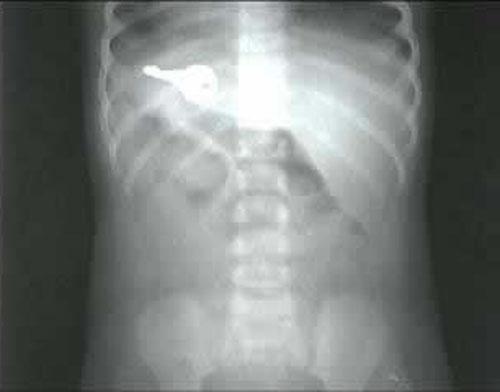

…И даже вилки…